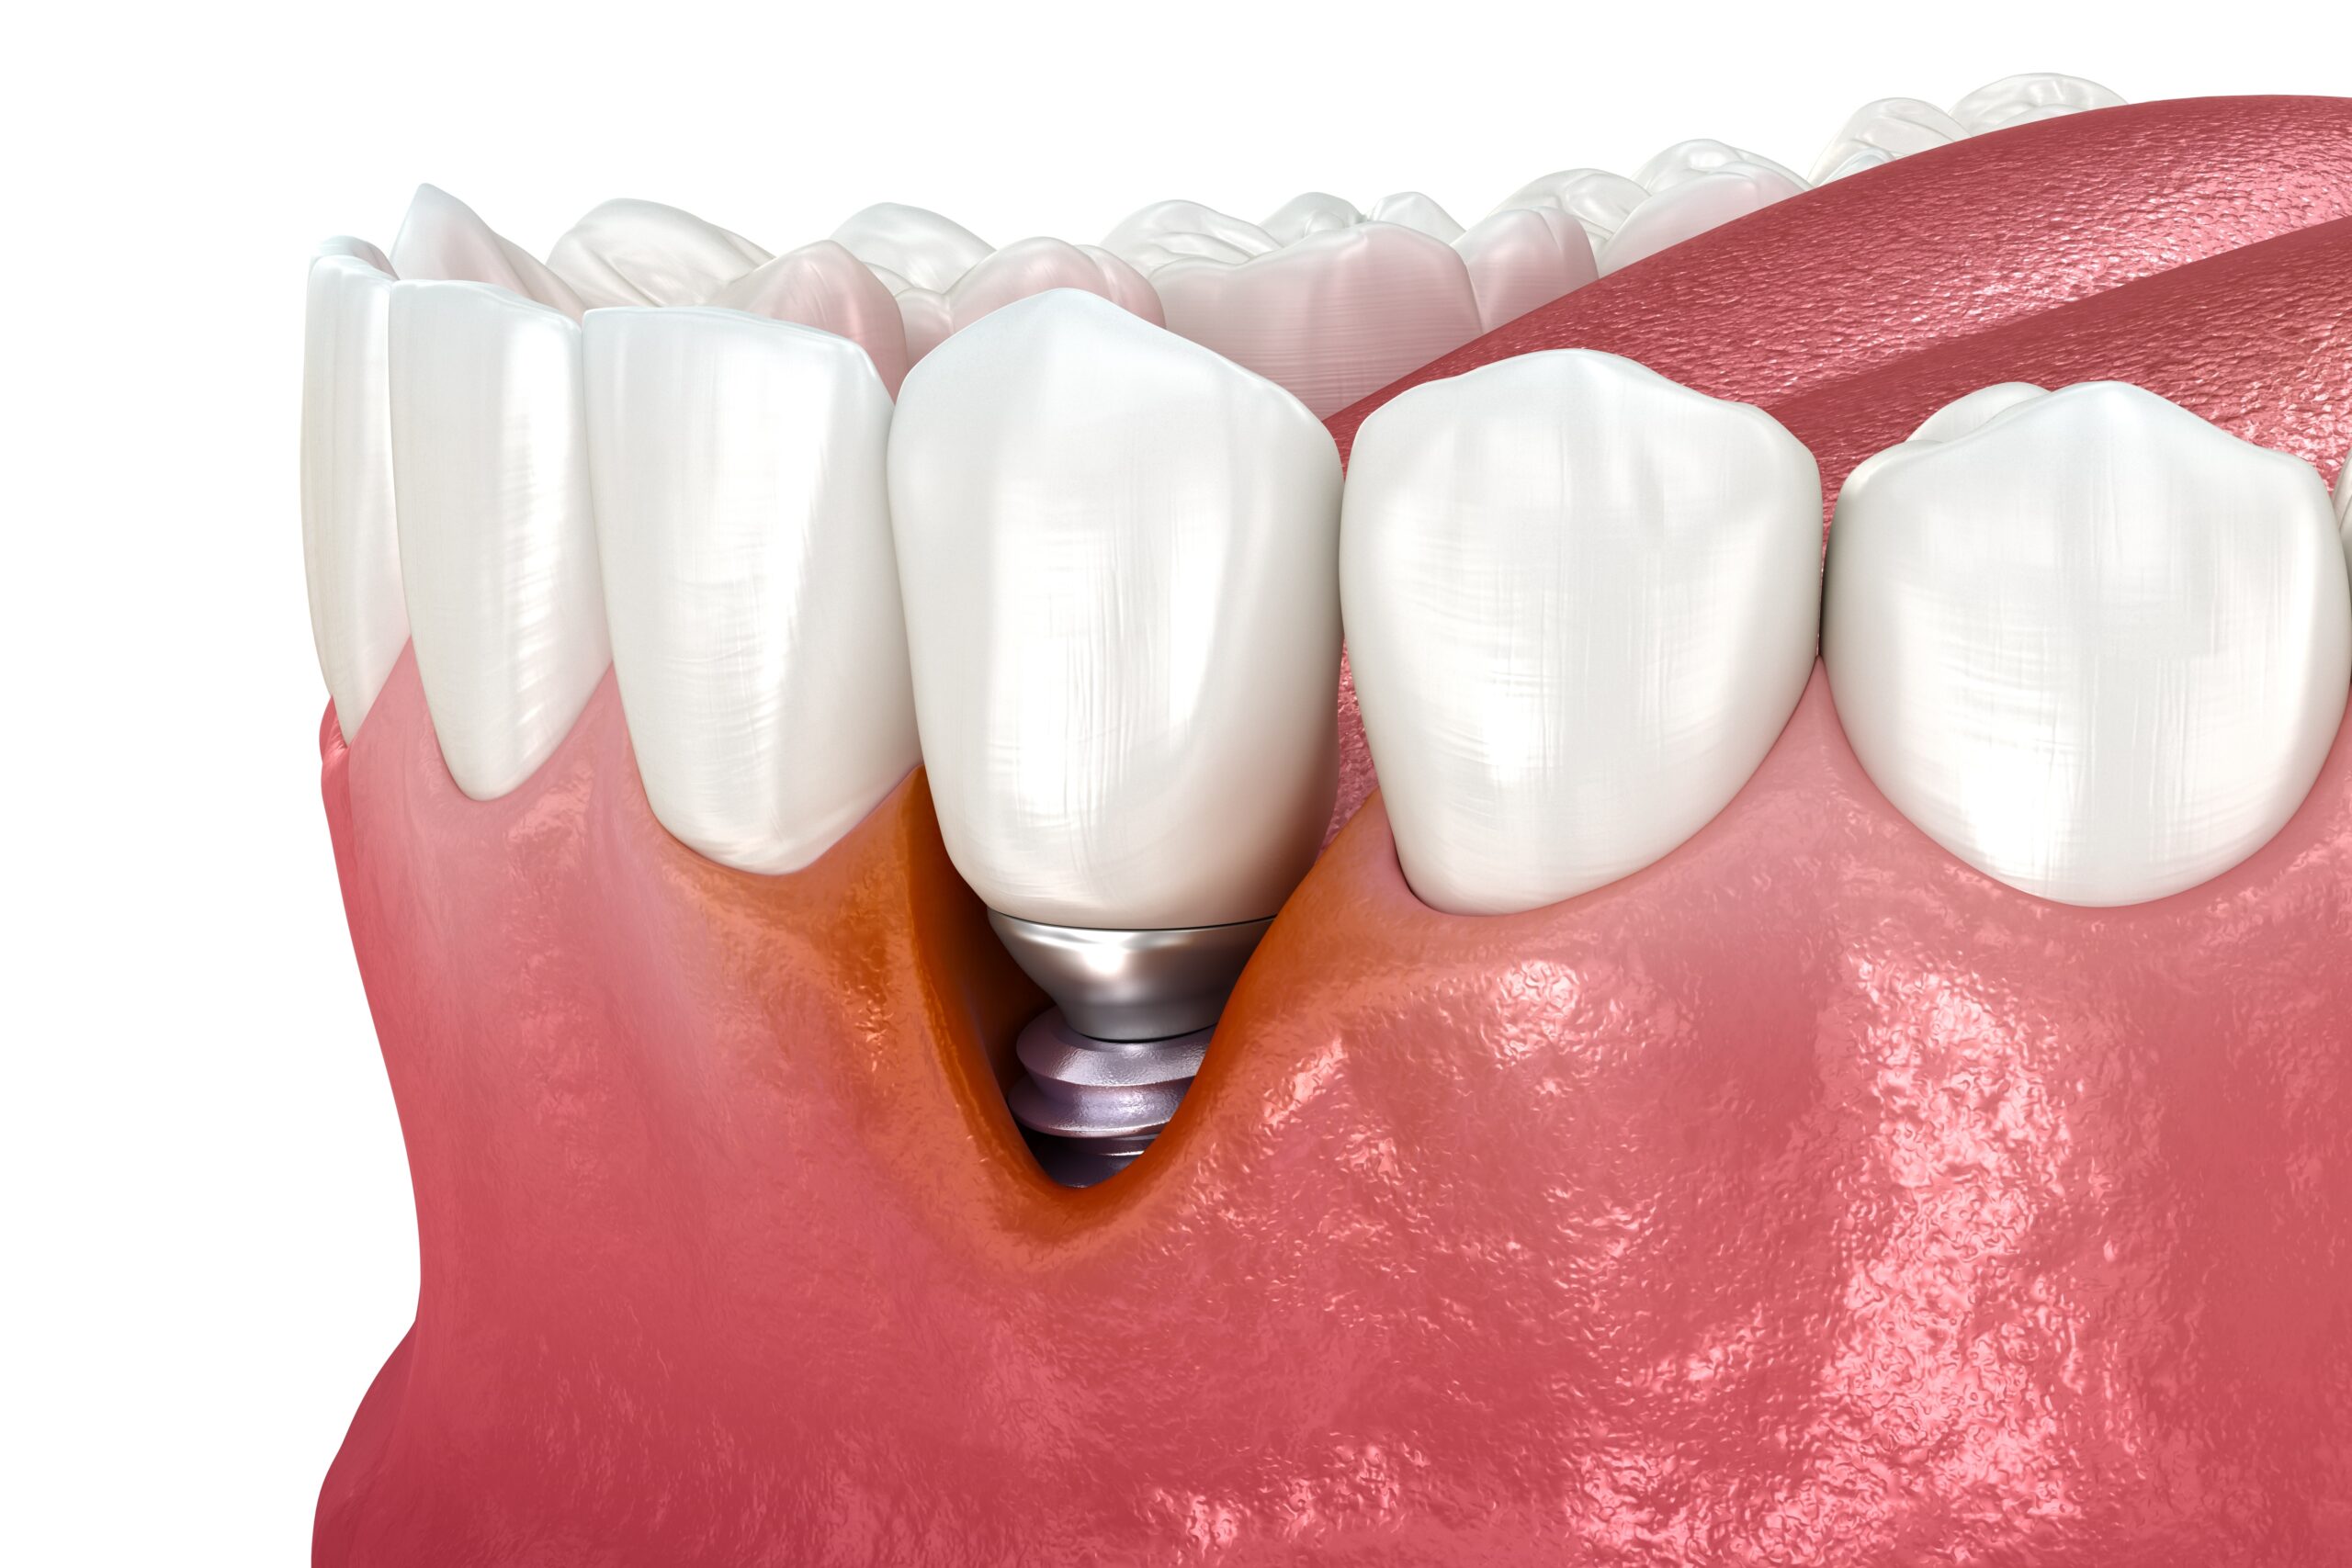

Single Dental Implants

A precise and natural-looking replacement for a single missing tooth, designed for long-term stability and esthetics.

What are dental implants?

Dental implants are small, titanium posts that are surgically placed into the jawbone beneath the gum line. They serve as a stable foundation for supporting artificial teeth, including crowns, bridges, and dentures. Dental implants are designed to mimic the root of a natural tooth, providing a strong and durable solution for tooth replacement that can last a lifetime with proper care.